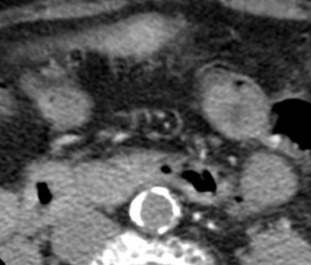

Cas

lereiche lerieche fontaine aorte aortique thrombus embol embolie occlusion iam syndrome lereiche